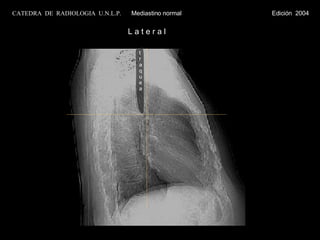

L a t e r a l traquea CATEDRA  DE  RADIOLOGIA  U.N.L.P.   Mediastino normal  Edición  2004

L a te r a l traquea CATEDRA DE RADIOLOGIA U.N.L.P. Mediastino normal Edición 2004